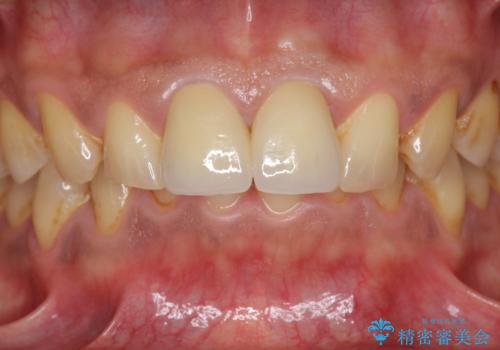

歯ぐきからの出血 膿が出る 前歯根管・セラミック治療

- 46万円(仮歯・根管治療・ファイバーコア・ジルコニアクラウン×2)費用は治療当時の料金となります